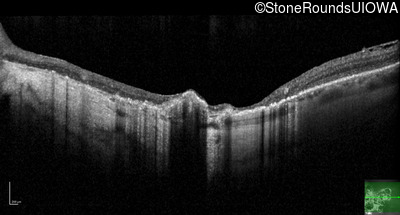

Optical Coherence Tomography - Left - 10/140

Exemplar / OCT Stack